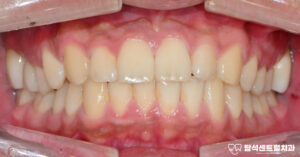

용현동 치과 외상으로 앞니 흔들림 있을 때, 치아를 보존하는 마지막 방법 : 잠간 고정술 설명 (+입술 봉합)

안녕하세요 용현동 치과 입니다. 빙판길 낙상, 구강 부상의 원인이 될 수 있습니다 겨울철에는 도로와 인도가단단하게 얼어붙는 경우가 많습니다.이런 빙판길에서 미끄러지면손을 짚기도 전에 얼굴부터바닥에 부딪히는 사고가 발생합니다. 특히 전치부는 충격에 취약한위치에…